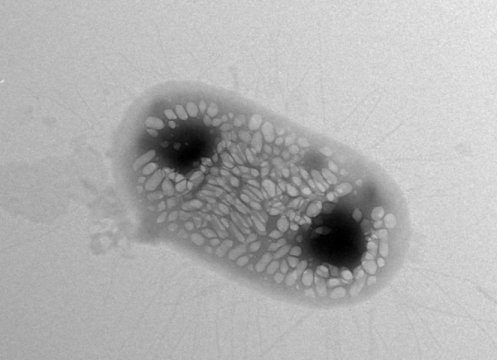

Shapiro bu keşfi 6 yıl önce suda yaşayan bakterilerde gaz dolu proteinler üzerinde çalışırken , gaz veziküllerinin ultrason dalgalarını yansıttığını gözlemledi. Sonrasında bu buluşu mide ve fare dokularında deneyerek görüntüleme yaptı.

Anabaena flos-aquae bakterisinde gaz vezikülleri üreten genleri izole ettiler. Yine başaramadılar. Fakat sonunda iki türü birleştirince çözüme ulaştılar.

Artık E.coli gaz vezikülleri üretebildiğinden ultrason görüntülemede kullanılabiliyor.